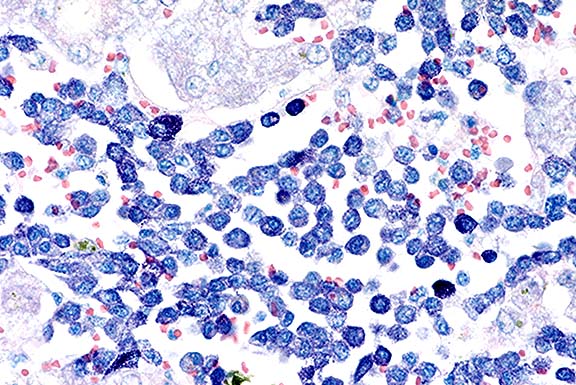

Case 9-2b. The mast cells contain sparse to numerous reddish-purple (metachromatic) granules in the cytoplasm. Giemsa. 40X

This case is an example of systemic mastocytosis in a cat. Metachromatic cytoplasmic granules were easily demonstrated in neoplastic mast cells with toluidine blue or Giemsa stains. Although gastroduodenal ulcers (probably secondary to histamine release) can develop in cats with this disease, none were found in this case. Disseminated intravascular coagulopathy may have contributed to the terminal clinical and hematologic findings.

AFIP Diagnoses: 1. Liver: Mast cell tumor, malignant, Domestic Shorthair cat, feline. 2. Liver: Necrosis, coagulative, centrilobular, diffuse.